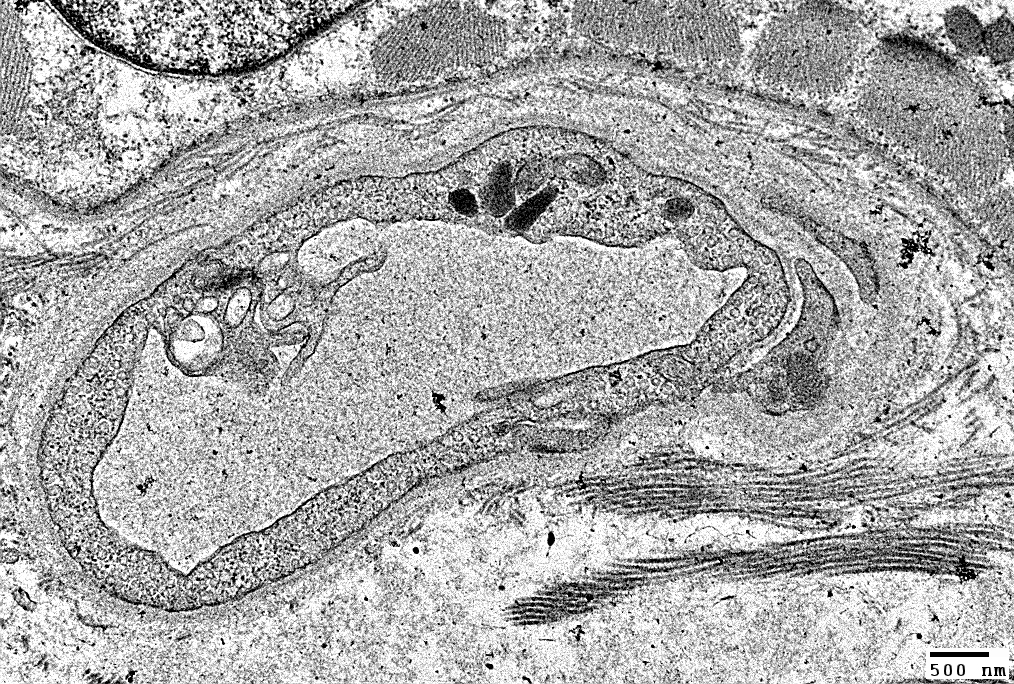

Myofiber Inclusions, Perinuclear

From R Schmidt